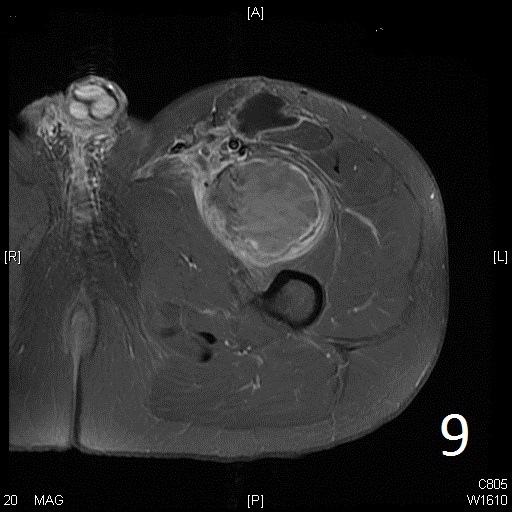

• Well defined heterogenous mass on T2W (Fig. 4, 9)

• On gadolinium, viable areas of tumor enhance, while areas of significant necrosis and hemorrhage do not enhance (Fig. 6).

Fig. 5-9: Axial and sagittal (Fig. 6) MRI shows a fibrosarcoma in the proximal quadriceps muscle that is isointense to muscle on T1W images, and a heterogeneous on T2W FS (Fig. 7, 8). The patient was treated with preoperative chemotherapy and the mass underwent extensive necrosis. The mass does not show any enhancement with contrast due to the extensive necrosis. There is only peripheral enhancement with contrast on T1W FS (Fig. 9).